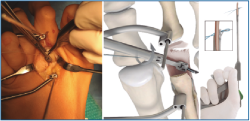

7. Fijamos la osteotomía de Weil con el acortamiento metatarsal deseado y previamente establecido (se recomienda un acortamiento mínimo de 2-3 mm) (Figura 12). Con la articulación MTF perfectamente reducida y el dedo en 30° de flexión plantar, tensamos las suturas recuperadas en el dorso de F1, hasta llevar firmemente la placa plantar a su base, y anudamos (Figura 13).

Figura 12. Fijación de la osteotomía de Weil con el acortamiento deseado (mínimo 2-3 mm).

Figura 13. Tensado y anudado individual de las suturas en el dorso de F1, confirmando la reducción estable de la articulación metatarsofalángica.